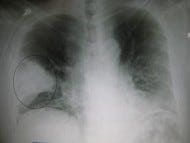

Antibiotics for community-acquired pneumonia: Is azithromycin out?